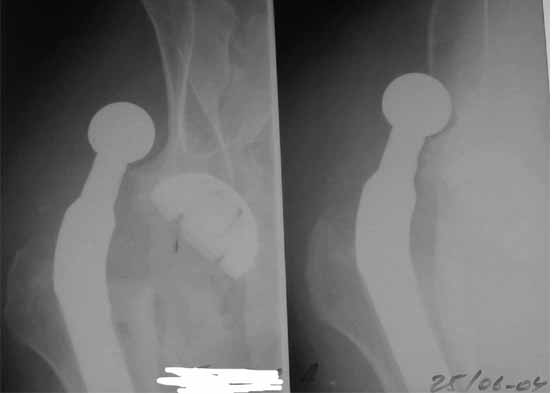

Во вложении - рентгенограммы после вывиха и после вправления.

С уважением Александр Артемьев